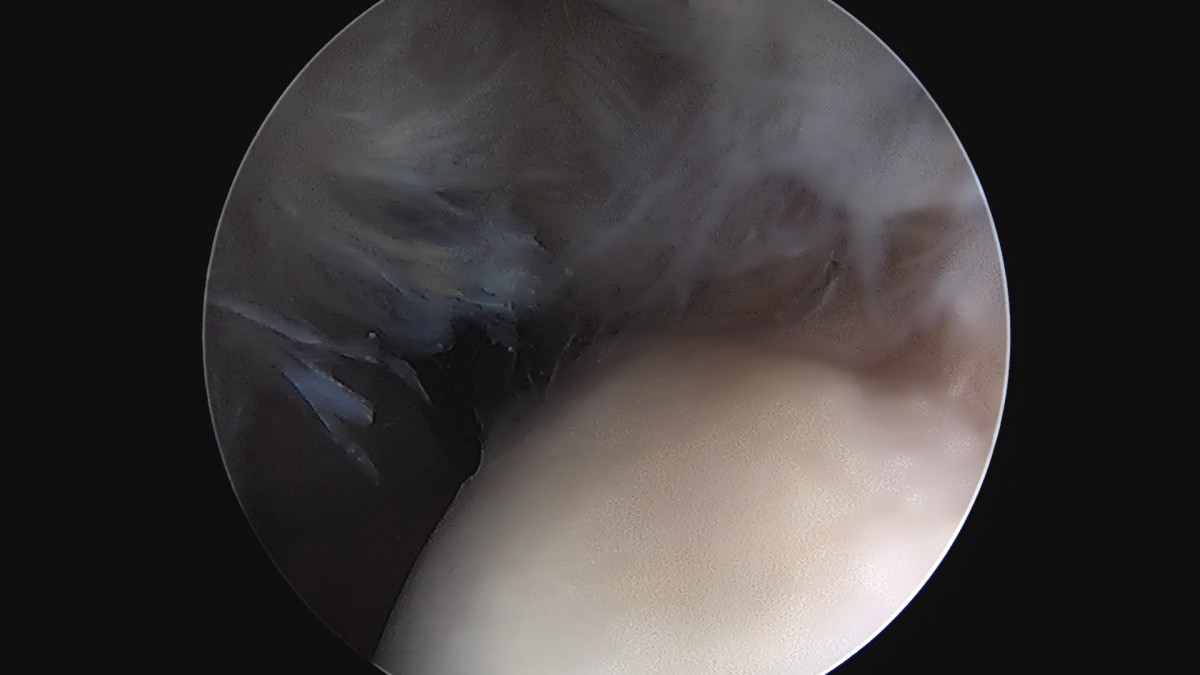

정지영원장님 어깨 회전근개 봉합술 임채O 환자

dae765e4d9ac96aee867c9d6292d8784_1758009112_4994.jpg